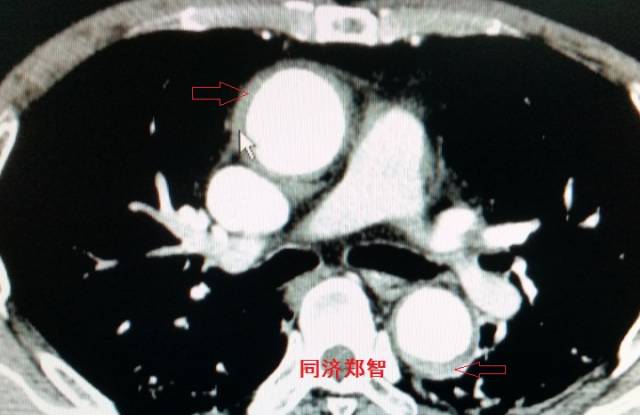

病例三

胸部平扫CT提示胸降动脉增宽(红色星形标记),CTA证实B型主动脉夹层伴降主动脉夹层动脉瘤形成。